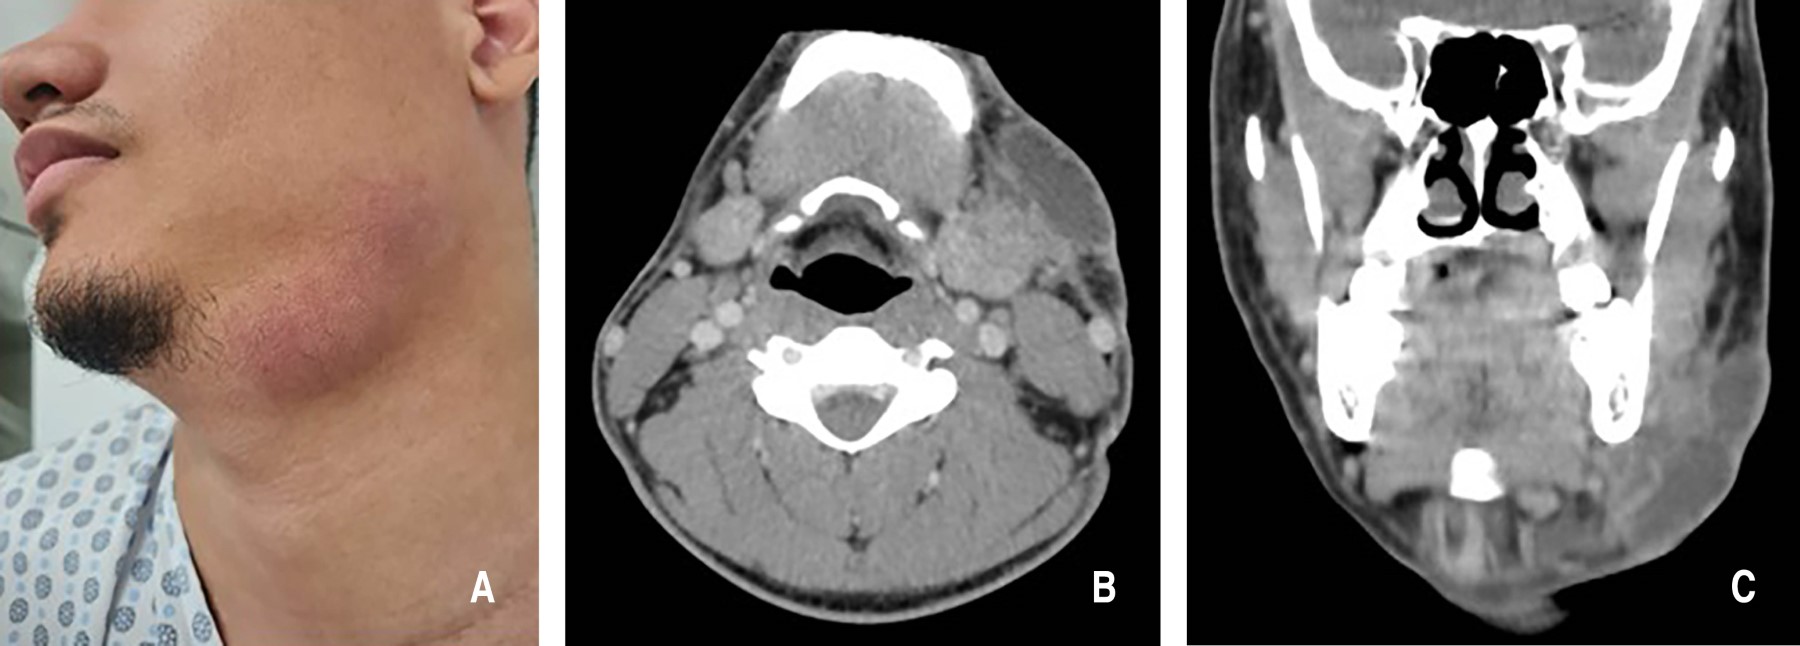

Cervical lymphadenitis as a manifestation of extrapulmonary tuberculosis. Literature review apropos of a case report

Tuberculosis is a chronic infectious disease that primarily affects the lungs but can also spread to other parts of the body, manifesting as extrapulmonary tuberculosis. We report the case of a 20-year-old male patient with tuberculous cervical lymphadenitis, diagnosed through imaging studies, laboratory tests, and biopsy. This led to the additional diagnosis of an underlying HIV infection. This case highlights the initial diagnostic challenge posed by extrapulmonary tuberculosis, emphasizing the importance of thorough knowledge of rare pathologies affecting the head and neck, the use of diverse diagnostic methods to ensure proper treatment, and the critical role of multidisciplinary management across related specialties.

Figure 3

Figure 4